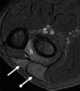

Complete AV communis